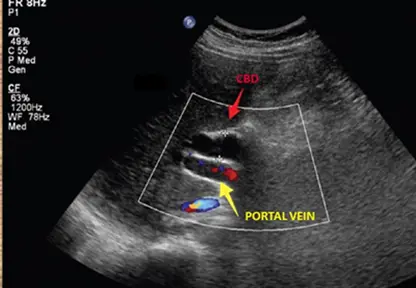

- 影像特徵:此為肝門處 (porta hepatis) 的腹部超音波彩色都卜勒 (Color Doppler) 影像。

- 解剖構造:影像中可見兩條平行的管狀無回音 (anechoic) 結構。下方的管狀結構標示為黃色箭頭的

PORTAL VEIN(門靜脈);上方的管狀結構標示為紅色箭頭的CBD(總膽管)。 - 血流訊號:利用都卜勒超音波可以輕易鑑別兩者。門靜脈內有明顯的彩色血流訊號(呈現紅藍色),而前方的總膽管內部則無血流訊號。

- 病理發現:正常生理情況下,總膽管的管徑應遠小於相鄰的門靜脈。然而,在此影像中,總膽管的管徑異常變寬,其直徑幾乎與下方的門靜脈相等。這種兩條粗細相仿的平行無回音管腔結構,即為典型的「雙管獵槍徵象」。